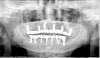

Wasja Опубликовано 9 июля, 2013 Поделиться Опубликовано 9 июля, 2013 Доброго времени суток, доктора! Пришел на контрольный осмотр пациент с работой 2009 г.в. Тогда как раз переходил с radix на adin, поэтому во рту получился такой микс. Вопросы почему и чем помочь. Работа тотальная и хотелось бы обойтись минимумом крови. Ссылка на комментарий

Zborzh Опубликовано 9 июля, 2013 Поделиться Опубликовано 9 июля, 2013 (изменено) Лучше бы переделать... Винты низкого уровня,как и работа . В позициях клыков имплантаты установлены протетически некорректно (далеко вне зоны воображаемого эстетического окна,слишком вестибулярно). Я бы тут посоветовал балочную конструкцию. Интересно мнение Doc'а. Изменено 9 июля, 2013 пользователем Zborzh Ссылка на комментарий

Mane Опубликовано 11 июля, 2013 Поделиться Опубликовано 11 июля, 2013 Доброго времени суток, доктора! Пришел на контрольный осмотр пациент с работой 2009 г.в. Тогда как раз переходил с radix на adin, поэтому во рту получился такой микс. Вопросы почему и чем помочь. Работа тотальная и хотелось бы обойтись минимумом крови. вы дали очень мало информации: по хорошему здесь бы выложить кт челюстей и нормальные фото зубных рядов и так далее. как я себе вижу - планировать временное протезирование на имплантах которые ОСТАЮТСЯ - планировать операцию по удалению части имплантов + установка новых имплантов + пластика кости (если требуется) + пластика десны. может так получиться что и не поставить сразу туда куда хочется. соответственно сначала пластика кости. потом уже имплантация. - осуществить операцию - осуществить временное протезирование - разбираться дальше (десна) Ссылка на комментарий

Wasja Опубликовано 14 июля, 2013 Автор Поделиться Опубликовано 14 июля, 2013 вы дали очень мало информации: по хорошему здесь бы выложить кт челюстей и нормальные фото зубных рядов и так далее. как я себе вижу - планировать временное протезирование на имплантах которые ОСТАЮТСЯ - планировать операцию по удалению части имплантов + установка новых имплантов + пластика кости (если требуется) + пластика десны. может так получиться что и не поставить сразу туда куда хочется. соответственно сначала пластика кости. потом уже имплантация. - осуществить операцию - осуществить временное протезирование - разбираться дальше (десна)Костной ткани достаточно во всех позициях имплантатов.Думаю убрать периимплантитные опоры и сразу поставить временные подковы.Хотя так неохота идти на тотальную переделку)... Ссылка на комментарий